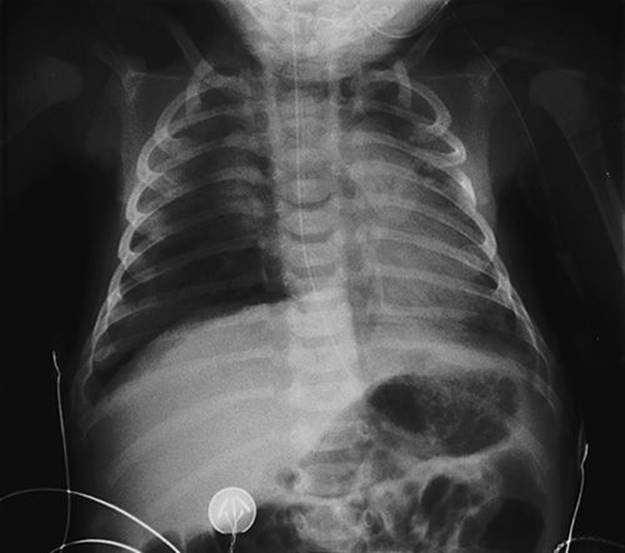

Respiratory distress syndrome (RDS) is caused by a deficiency of surfactant and is commoner in pre-term infants (0.1% at term vs 30% at 28 weeks). Surfactant, a complex lipoprotein consisting largely of phosphatidyl choline, is synthesized by type II pneumocytes within the alveoli and is important in reducing surface tension, allowing the alveolus to expand. Hypoxia, acidosis and hypothermia reduce surfactant production; antenatal steroids increase production and thereby reduce the incidence of RDS. Clinically there is tachypnoea, grunting and intercostal recession commencing within the first 4 h of life, low oxygen saturations requiring oxygen and the chest X-ray demonstrates a generalized reticulogranular appearance referred to as like ‘ground glass’ (Fig. 50.1). Some babies improve with supplemental oxygen or continuous positive airways pressure (CPAP), but increasing respiratory distress and oxygen requirements are indications for intubation and administration of artificial surfactant via an endotracheal tube.

FIG. 50.1Respiratory distress syndrome following emergency caesarean section.

The mother had diabetes, which predisposes to respiratory distress syndrome. Note the ground-glass appearance of the lungs.